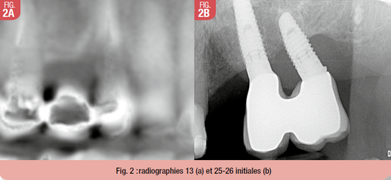

L’examen clinique endo-buccal montre notamment une lésion dentinaire importante sous couronne de 13, support de bridge 13-14-15 (Fig. 2), une absence de 24 avec un site de cicatrisation normal, une 26 supra-implantaire avec un sondage provoquant une suppuration sulculaire.

L’examen radiologique montre une lésion radio-claire autour de l’implant 26 à la radio rétro-alvéolaire (Fig. 2) et l’image issu du CBCT montre une crête fine en place de 13-14, et une hauteur osseuse sous-sinusienne réduite secteur 2.